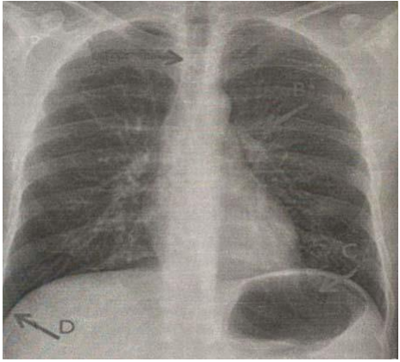

Qual a melhor sequência define as estruturas anatômicas apontadas (A, B, C e D)

abaixo:

(A) esôfago, (B) hilo pulmonar esquerdo, (C) bolha gástrica, (D) seio costofrênico

direito.

(A) traqueia, (B) hilo pulmonar esquerdo, (C) bolha gástrica, (D) seio costofrênico

esquerdo.

(A) traqueia, (B) aorta, (C) bolha gástrica, (D) seio costofrênico direito.

(A) pulmão, (B) coluna vertebral, (C) bolha gástrica, (D) seio costofrênico direito.